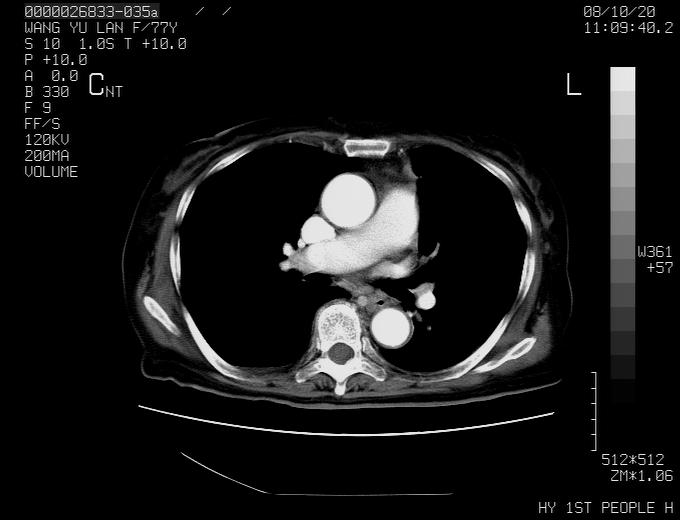

女性,77岁,胸部疼痛半月。左上肺团块影,本人考虑血管畸形,请分析

动脉期未见大血管同步强化,首先考虑周围型肺癌

动脉期病灶近中线侧可见星芒状与大血管同等强化密度,支持考虑血管畸形伴血栓形成,动脉期不曲型,不除外周围型肺癌

1、考虑avm可能性大。2、纵隔有肿大淋巴结,左肺上叶有炎性病变,不排除肺癌并转移可能。